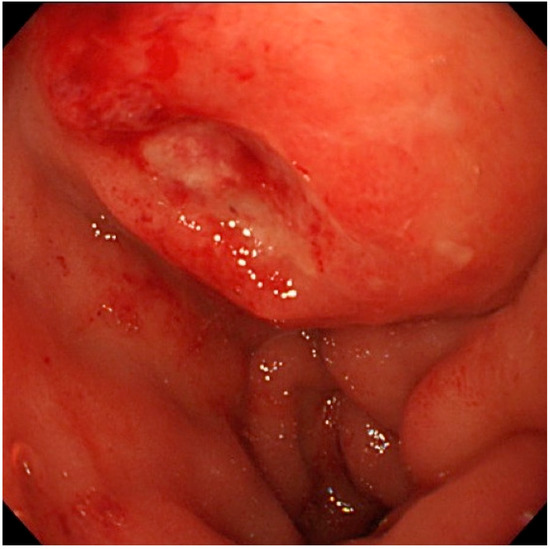

Figure 2.

Endoscopic view of the duodenal bulbs. A hemispheric submucosal tumor with apical erosion was recognized.

An 82-year-old Japanese female was referred to our hospital after a month of complaints of upper abdominal discomfort. First, she visited the nearest hospital and underwent upper gastrointestinal endoscopy that pointed multiple erosions and an extrinsic compression at the posterior pylorus. Medication had been initiated using nizatidine, rebamipide and oxetacaine, but it was not effective. She had a history of hypertension, but her family history was unremarkable. Blood tests showed modestly elevated IgG (1950 mg/dL, normal range: 870–1700 mg/dL) and C-reactive protein (0.43 mg/dL, normal range: ≤ 0.3 mg/dL) but normal readings for other factors, including serum tumor markers (carcinoembryonic antigen, carbohydrate antigen, and soluble IL-2 receptor), HbA1c, and IgG4 (66.1 mg/dL, normal: 4.5–117 mg/dL). Enhanced computed tomography (CT) demonstrated an ill-enhanced mass, 5 cm in size but with unclear margins, located at the pancreas head (Figure 1a,b). Upper gastrointestinal endoscopy revealed a submucosal tumor (SMT) with an apical erosion approximately 1.5 cm in size at the duodenal bulbs (Figure 2). Several faintly enlarged lymph nodes were seen around the pancreas head, but no nodules suggestive of metastasis were visible in the liver or the lungs. Endoscopic ultrasonography (EUS) demonstrated a heterogeneous, low-echoic mass at the pancreas head and body, but no adhesion to the common bile duct. EUS elastography revealed a hardness of the pancreas lesion (Figure 3). Forceps biopsy (Radial Jaw™4, Boston Scientific Japan, 2.2 mm, Tokyo, Japan) from the duodenal SMT was not informative, but EUS-guided fine needle aspiration biopsy (FNAB) showed abundant spindle myofibroblast tissues with eosinophilic and lymphoplasmacytic cell infiltration (Figure 4). FNAB was performed with two punctures from the duodenal bulbs, with each puncture performed with 10 strokes using a 22-gauge Franseen-tip needle (Acquire™, Boston Scientific Japan) with 10 mL of negative pressure. No malignant cells were seen. The spindle cells were positive for anti-smooth muscle antibody (ASMA) and desmin but negative for discovered on GIST-1 (DOG-1), c-Kit, CD34, S-100, and ALK. Only six IgG4-positive cells were recognized in high-powered views, and no obliterative phlebitis or storiform fibrosis was detected. These findings led to the diagnosis of IMT.